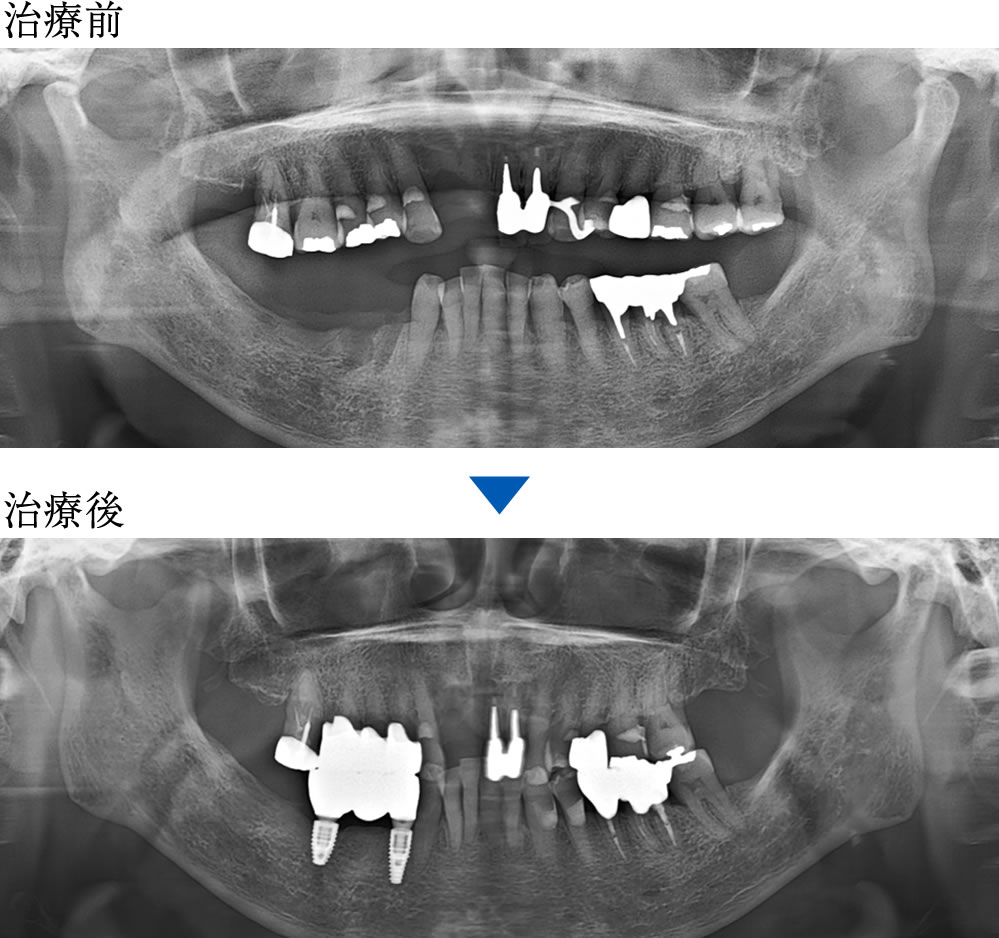

治療前後の比較

インプラント治療により、固いものもしっかり噛めるようになったとのことでした。また、歯肉移植を併用したことで、インプラント周囲の清掃性も向上しました。

| 年齢・性別 | 70代 女性 |

|---|---|

| 治療期間 | 8ヵ月 |

| 治療回数 | 20回 |

| 治療費(税込) | 1,725,000円 |

| リスク・注意点 | 外科処置には術後麻痺等のリスクがあります。 骨の状態によっては治療期間が長くなる場合があります。 |